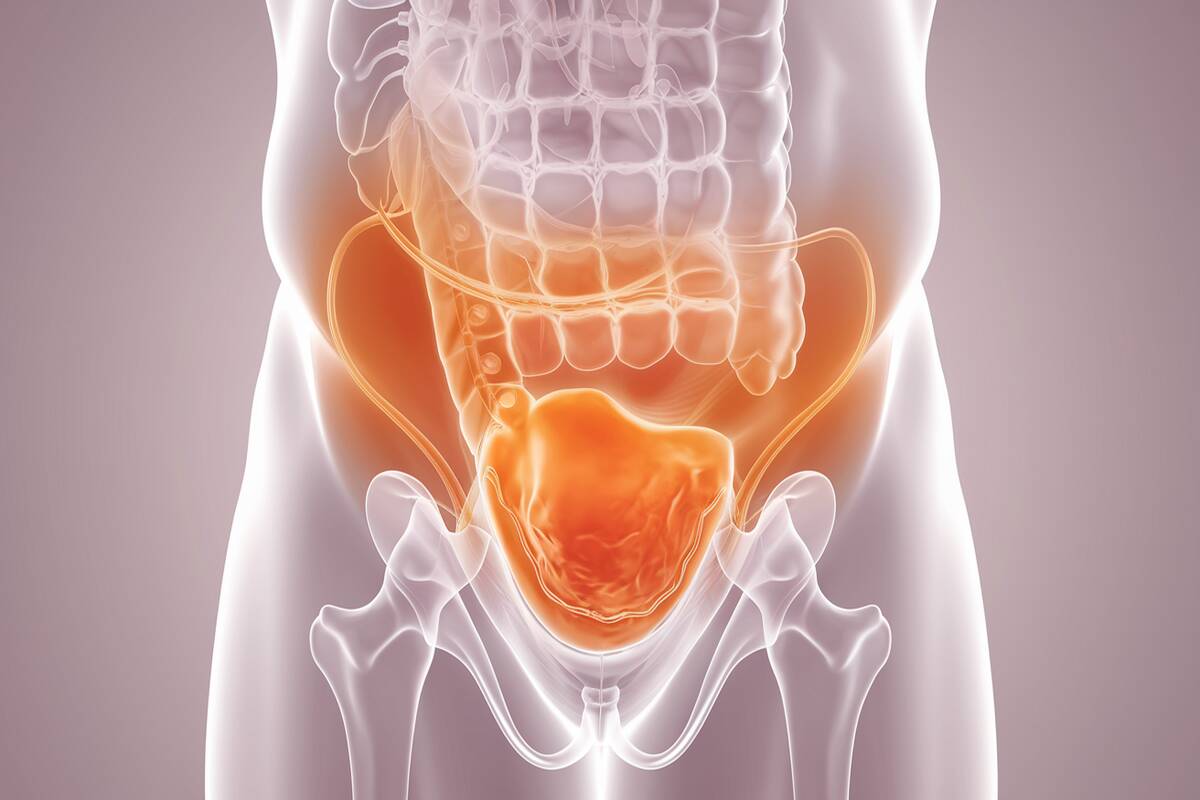

Bowel leakage is not automatically a sign of cancer, but it can be a warning symptom in certain situations. Cancers affecting the colon, rectum, or anus may interfere with the nerves, muscles, or passageways that regulate bowel control.

Cancer can cause bowel leakage when tumors block or press against the rectum, anus, or nerves, disrupting standard control of bowel movements. Additionally, cancer treatments like surgery or radiation may weaken muscles or damage tissues, leading to incontinence.

- Tumors in the colon, rectum, or anus may press against bowel muscles or nerves.

- This pressure disrupts normal function, leading to leakage.

4. Intestinal Obstruction

- Large tumors can block the normal flow of stool.

- This obstruction causes pressure that forces stool to be expelled involuntarily.

Cancers Commonly Associated With Bowel Leakage

Cancers commonly associated with bowel leakage include colorectal, rectal, and anal cancers, as these directly affect the digestive tract and bowel control. In some cases, gynecological cancers such as cervical or ovarian cancer can also contribute to leakage by spreading to nearby tissues and nerves.

| Colorectal Cancer | Tumors in colon/rectum disrupt bowel control |

| Rectal Cancer | Damages rectal nerves and sphincter muscles |

| Anal Cancer | Affects anal sphincter, leading to leakage |

| Gynecological Cancers | Pressure on rectum causes bowel dysfunction |

- One of the leading cancers associated with bowel leakage.

- Tumors in the colon or rectum can restrict the passage of stool and affect muscle control.

- Affects the rectum, where stool is stored before elimination.

- Tumors may damage nerves and muscles directly responsible for continence.

- Ovarian and cervical cancers can press against the rectum.

- Women may experience leakage due to pelvic pressure and nerve disruption.